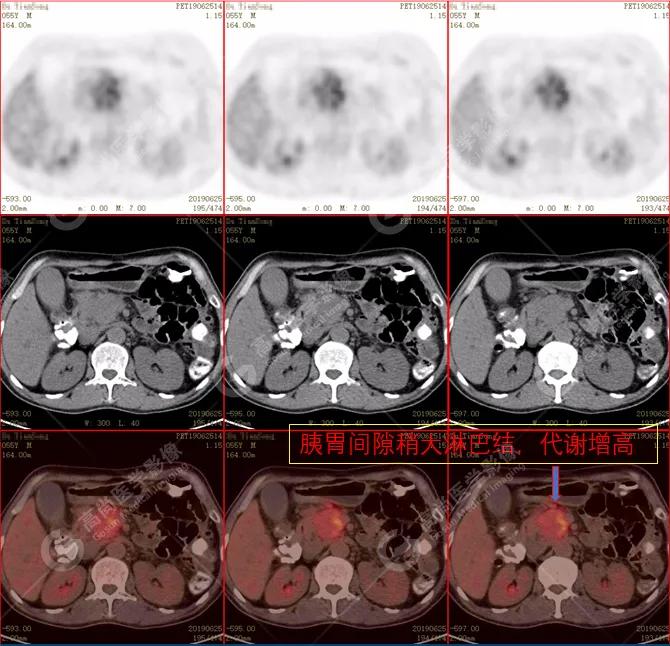

(2)胰周(胰胃间隙)稍大淋巴结,代谢增高。

• PET/CT:多呈弥漫性代谢增高,少数呈局灶性结节状高代谢灶。

•CT:胰腺体积 不同程度弥漫性肿大 ,密度减低或正常,增强扫描动脉早期强化低于正常胰腺,延迟期 均匀一致强化。胰周脂肪间隙多数清晰 ,少数可见少量条状异常密度或信号(轻度炎性反应)。

•常合并其他自身免疫性疾病(腹膜后纤维化),全身或局部淋巴结肿大、浆膜腔积液等。